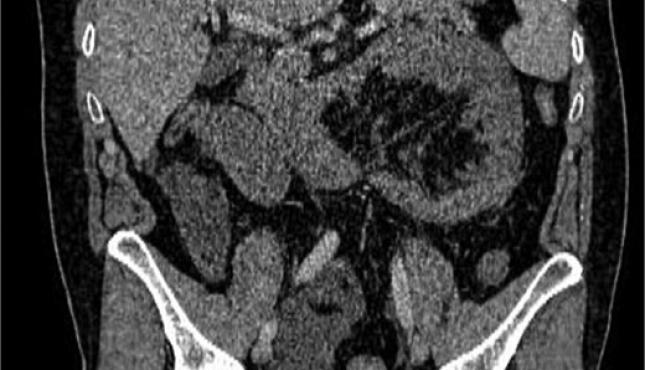

أظهرت الفحوصات والتصوير الطبي وجود فتق داخلي نادر أدى إلى احتباس جزء من الأمعاء الدقيقة داخل تجويف غير طبيعي في البطن، ما تسبب في انسدادها وانقطاع التروية الدموية عنها.

ويُعد هذا النوع من الحالات من الأسباب النادرة لانسداد الأمعاء، لكنه قد يتحول بسرعة إلى حالة مهددة للحياة إذا لم يتم التدخل الجراحي العاجل.

وخلال العملية اكتشف الأطباء أن جزءًا من الأمعاء الدقيقة تعرض للاختناق والتلف نتيجة الفتق الداخلي.

وقام الفريق الجراحي باستئصال نحو 60 سنتيمترًا من الجزء المتضرر من الأمعاء، ثم إعادة توصيل الأمعاء السليمة جراحيًا، مع معالجة سبب الفتق بشكل كامل.